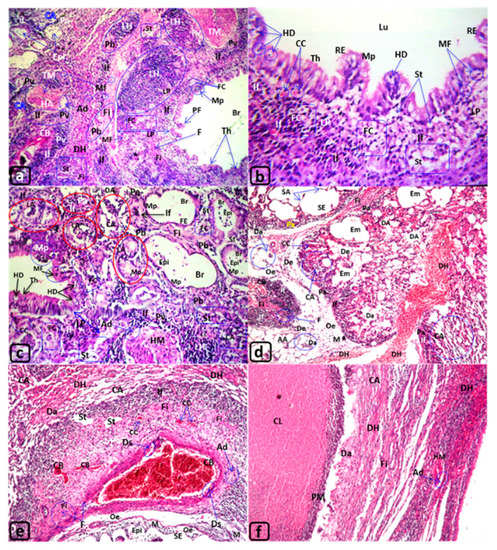

| Trachea of Rats Exposed to MTBE Vapor Inhalation 60 µL/3 min/day for 3, 6, or 12 Months | |||||

|---|---|---|---|---|---|

| Groups | G1 | G2 | G3 | G4 | |

| MTBE exposure | Non exposed | MTBE 60 µL/3 min/day/for 3 months | MTBE 60 µL/3 min/day/for 6 months | MTBE 60 µL/3 min/day/for 12 months | |

| Results | |||||

| Figures | (Figure 1a) | (Figure 1b–d) | (Figure 1e,f) | (Figure 2a–f) | |

| Tracheal lumen “Lu” | Clear | - | - | Epithelialization Epi | |

| Necrotic cells “NC” | |||||

| Mucosal layer: Lining “respiratory “epithelia “RE” | Normal | Ulceration “MUl” | Desquamation “Ds” | ||

| Deciliation “Dc” | Flattened “FE” | ||||

| Polyp formation PF | Degenerative epithelium “DE” | ||||

| --- | Hydropic degeneration “HD” | ||||

| Hyperplasia “Hp” | |||||

| Metaplasia “Mp” | |||||

| Lamina propria “LP” | Normal | --- | Tracheal adenomas “TA” | ||

| Inflammatory cells “IF”, | |||||

| Congested blood vessels “CB”, | |||||

| edema “Oe”, | |||||

| Fibroid changes “Fi” | |||||

| Foam cells “FC” | |||||

| Hyaline cartilage “HC” | Normal | Perichondrial thickening “PeT” | |||

| Deformation “Df” | Increase in diameter “Di” | Di with Degeneration DHC | |||

| Peritracheal connective tissue “CT” | Normal | --- | --- | Foam cells “FC”, fatty degeneration “FD” | |

| --- | --- | Monocytic infiltration “M” | |||

| Edema “Oe” | |||||

| Blood vessels of CT | Normal | Dilated and congested blood vessels “CB” | |||

| Thyroid gland | Normal | ---- | ---- | Degenerated thyroid follicles “DT” | |

| Lung of Rats Exposed to MTBE Vapor Inhalation 60 µL/3 min/day for 3, 6, or 12 Months | |||||

| Figures | (Figure 1a) | (Figure 3b–d) | (Figure 3e,f) | (Figure 4a–f) | |

| Lumen of Bronchioles “Br” | Normal, Clear | Dilatation in some bronchi “DB” | |||

| Lining epithelia of bronchioles “Br” | Normal | deciliation “Dc” and shortening | --- | ||

| --- | Metaplasia “Mp” | ||||

| --- | Polyp formation PF | Hydroid degeneration “HD” | |||

| Peribronchiolar “Pb” and perivascular “Pv” connective tissue “CT” | Normal | --- | --- | Pulmonary fibrosis Fi | |

| --- | --- | Foam cells “FC” | |||

| --- | --- | Steatosis “St” | |||

| Lymphocytic infiltrations “If” | |||||

| large lymphoid hyperplasia “LH” | |||||

| Lumen of air alveoli | Normal, Clear | --- | --- | Collapsed alveoli CA | |

| --- | --- | Dilated lumen with Epithelialization Epi | |||

| Hemorrhages “H” | H + Diffuse “DH” | ||||

| Epithelia of air alveoli “AA” | Normal | Emphysematous changes “Em” | Severe Em | ||

| Desquamation “Ds” | |||||

| Shortening with deciliation “Dc” | Degenerated (De) in some air alveoli (Da) | De, Da, metaplasia “Mp”, or thickening “Th” | |||

| --- | --- | Polyp’s formation “PF” | |||

| Interalveolar septa of air alveoli “IA” (Interalveolar CT) and perivascular CT | Normal | Destructed septa “SD” | |||

| Inflammatory cells infiltrations “If” | If with monocytic infiltration “M” | ||||

| Destructed septa “DS”, sever dilated (DV), congested vessels (CB), & capillaries (CC) | Lymphoid hyperplasia “LH” | ||||

| Adenomatous changes (lung adenoma) “LA” | |||||

| Abscess with central liquefaction “CL” covered by pyogenic membrane “PM” | |||||

| Fibroid changes “Fi” | “Fi” with diffused fibrocytes “F” | steatosis (St) with Fi | |||

| --- | --- | Numerous lipid-laden macrophages “Foam cells” “FC” | |||

| ---- | ---- | Mitotic figure “MF” | |||

| Focal hemorrhages “H” | H + Diffuse DH | ||||

| Blood vessels of CT “BV” | Normal | Dilated vessels “DV” | Occluded lumen | ||

| Congested blood vessels “CB “, Dilatated and Congested blood capillaries “CC” | |||||

| Arterial alterations in tunica intima “TI”, tunica media “TM”, and tunica adventitia “Ad”, | Normal TI, TM & Ad | --- | --- | Desquamation “Ds” in TI | |

| --- | --- | Thickening TM & Ad | |||